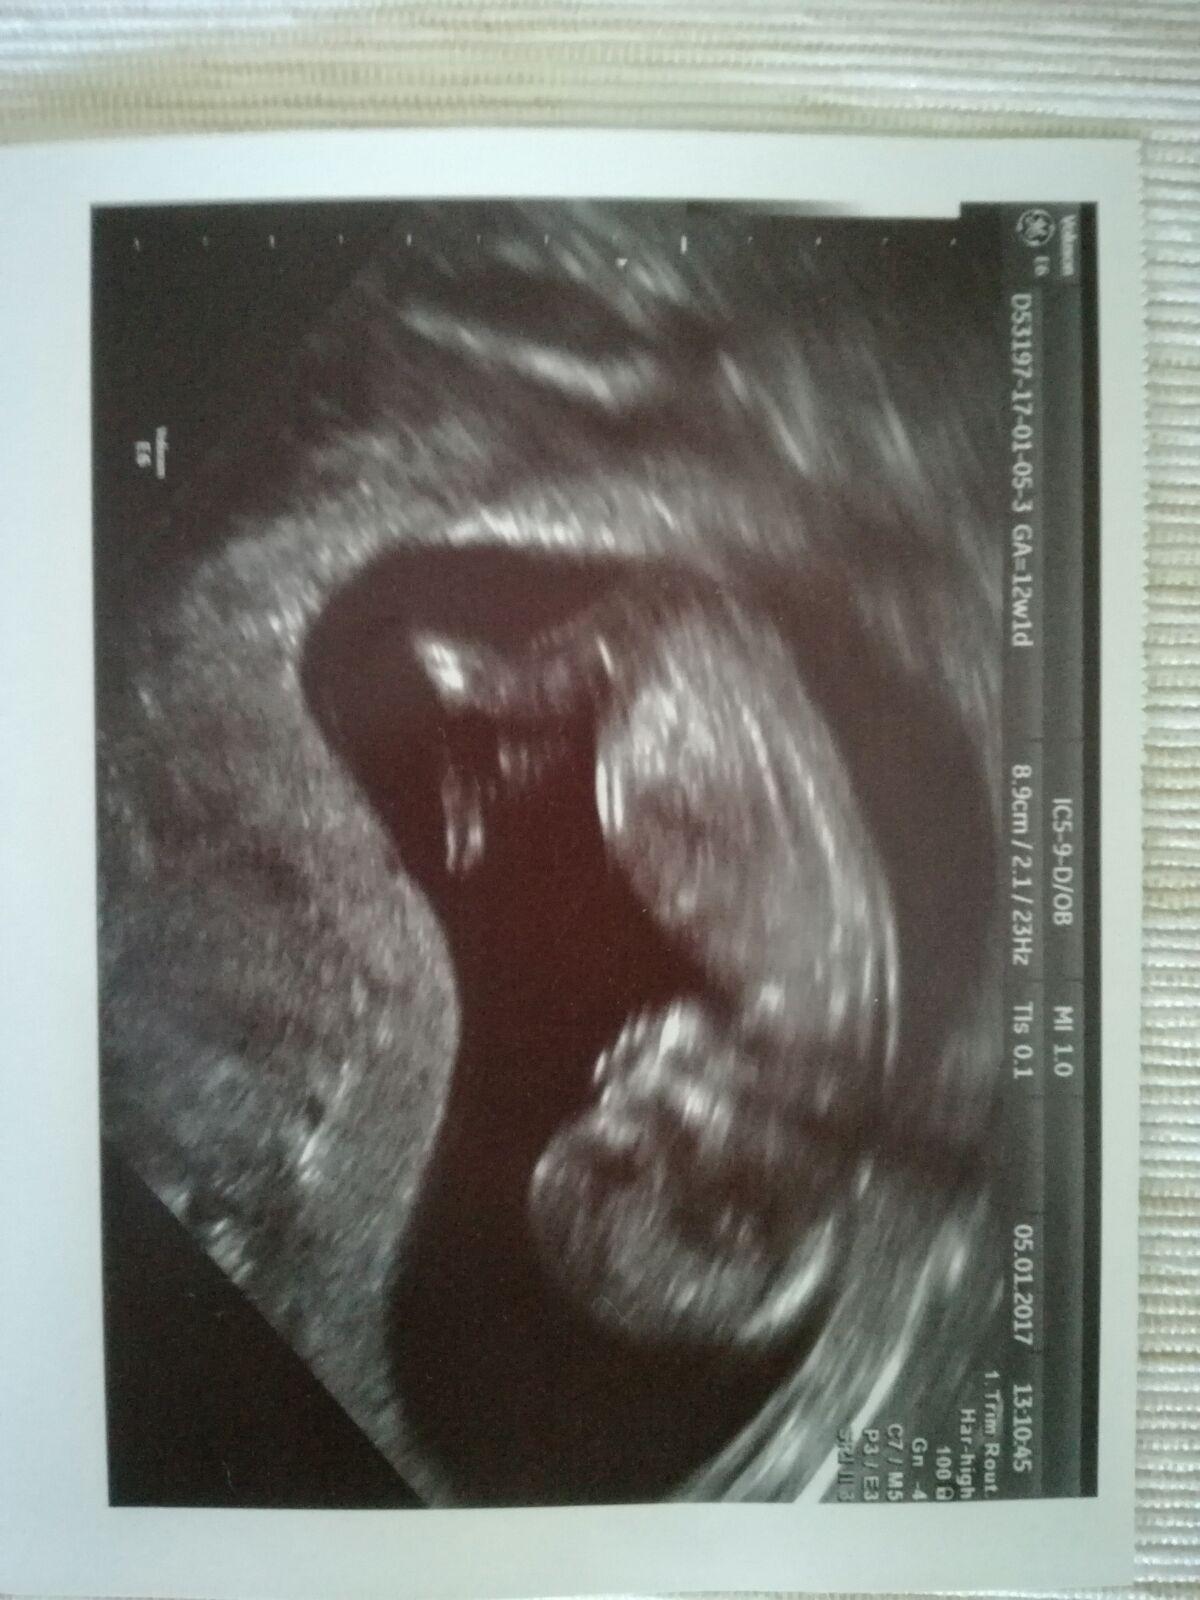

Ahoj holky, krásný nový rok! 👍 Já byla dneska na kontrole a pinďa se neukázal, tak máme zatím potvrzeno jen z prvotrimestrálního screeningu, uvidím co za měsíc, ale asi už mu neupadne 👶😅

AHOJ, PRIKLADAM DVE FOTECKY ZE SCREENINGU.. OBE 13 + 1... PRVNI FOTO JE NAS DVOULETY CHLAPECEK.. JE VIDET VYBEZEK NAHORU, DRUHE FOTO , JE MIMINO, KTERE MAM TED V BRISKU.. DLE LEKARKY TO VYPADA NA HOLCICKU.. A JA ZATIM ASI MOHU SOUHLASIT..... NA DRUHE FOTCE VYBEZEK NAHORU NENI.... TAK OPET UVIDIME ZDA MI TO MA LEKARKA ZA TRI TYDNY POTVRDI...